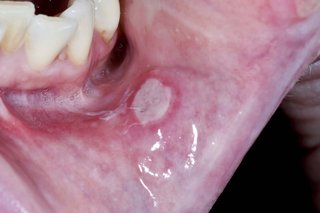

A large, white, circular mouth ulcer on the inside of the bottom lip.

Mouth ulcers usually appear inside the mouth on the cheeks or lips.